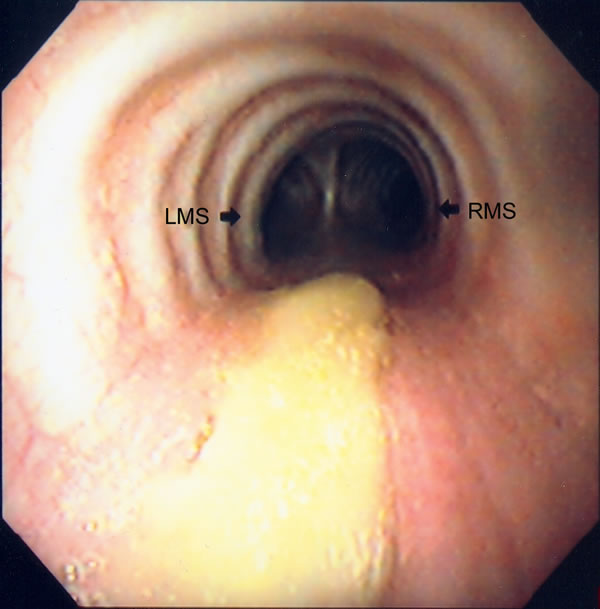

The patient was taken to the intensive care unit still intubated. A few hours later, he underwent bronchoscopy to clear secretions and was extubated. His postoperative stay was uneventful. A follow up flexible bronchoscopy was performed on postoperative day (POD) # 6 revealing a healing suture line on the membranous region of the trachea (Figure 6). The patient’s chest tube demonstrated a small air leak on POD # 7 and he was discharged with the tube connected to a minipleurovac on POD # 8. He underwent bronchoscopy one week later, which revealed a healed suture line with minimum granulation tissue (Figure 7); furthermore, there was no evidence of air leak and the chest tube was removed.

| Figure 6: Bronchoscopic view of repair on post-operative day #6. | Figure 7: Bronchoscopic view of the repair at 2 weeks. |